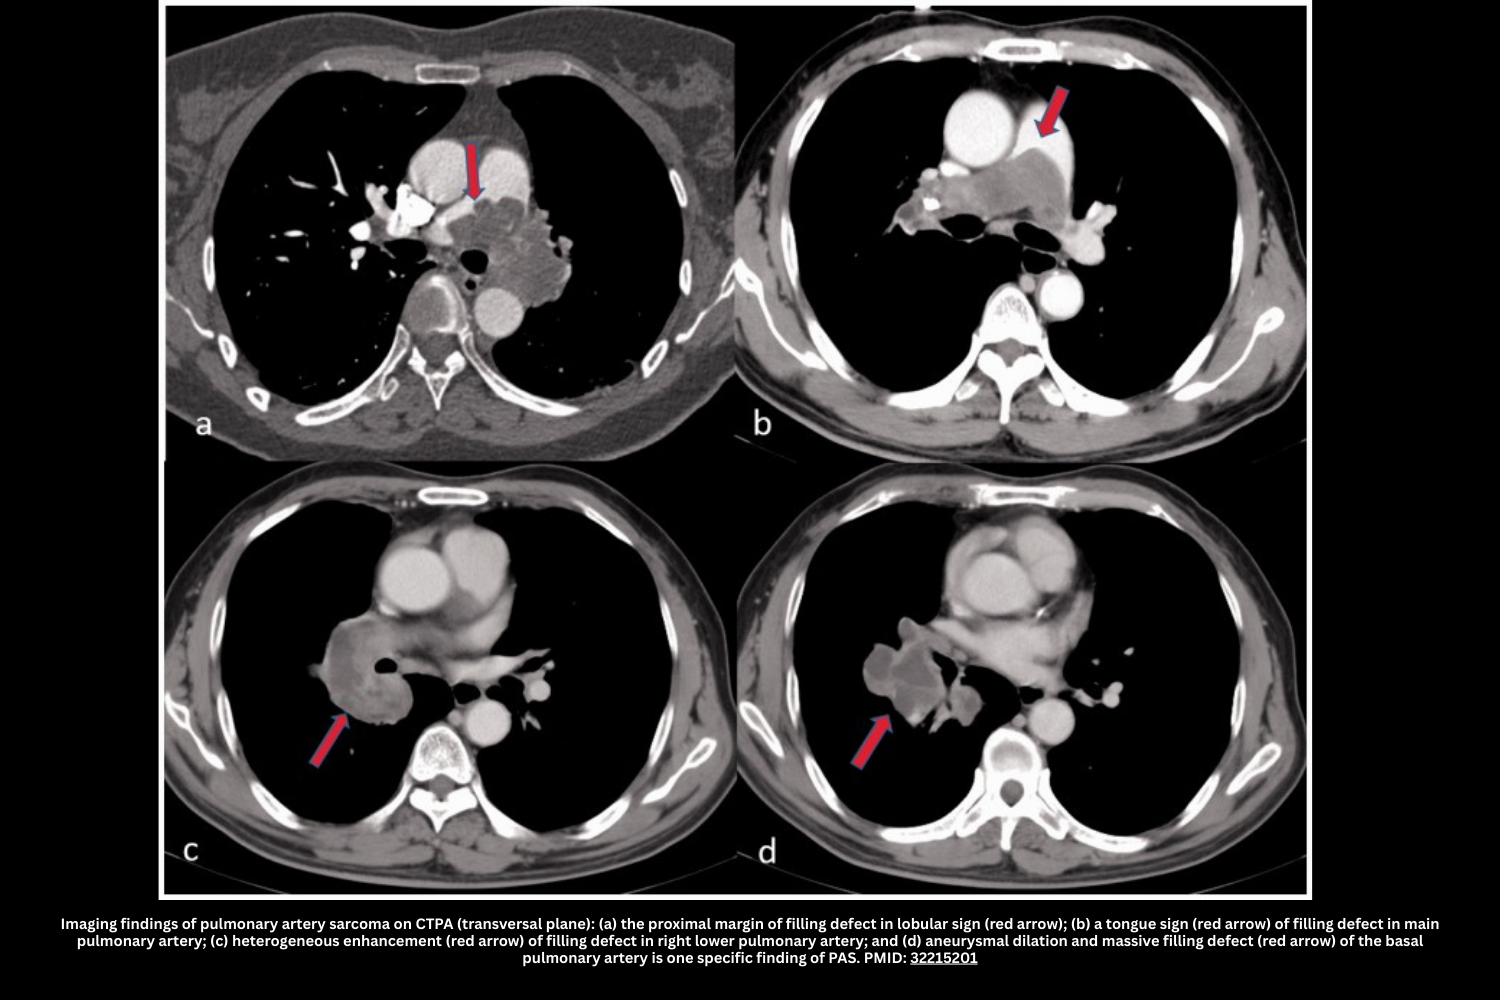

III. Pulmonary Artery Sarcoma (PAS)

Pulmonary artery sarcoma (PAS) is a rare but critical mimic of pulmonary embolism. Unlike embolic disease, it represents a primary malignant tumor of the pulmonary artery, most often diagnosed in middle age.

◾️Key Features (CTPA & Clinical Context):

- Epidemiology & Presentation

- Typically presents between 45–55 years; rare in patients <30.

- Gradual onset of pulmonary hypertension and RV failure over months.

- Symptoms are often mild compared to dramatic CT findings.

- Red flags: Constitutional symptoms (fever, weight loss, night sweats) and failure to improve with anticoagulation.

- 🩻Imaging Clues

- Most common findings:

- A Lobulated or nodular appearance is often seen.

- A single, central lesion tends to occur (unlike a pulmonary embolism, which frequently causes multiple, bilateral filling defects).

- Filling of the entire arterial lumen (“eclipsing vessel sign”).

- More specific features that may occasionally be seen:

- Vessel expansion due to mass effect.

- Invasion of the lung parenchyma or mediastinum.

- Hematogenous metastasis causes randomly distributed nodules in the lung parenchyma.

- Calcification may occur; if encountered, this suggests against PE (although calcification can also occur in the context of chronic thromboembolic pulmonary hypertension).

- Lesions may have low attenuation. Heterogeneous contrast enhancement may occur (although this won’t be captured on a CT angiogram).

- Diagnosis

- Consider when CT findings are disproportionate to symptoms or when “PE” does not resolve with treatment.

- MRI or PET can support diagnosis; tissue confirmation via endovascular biopsy or surgical resection.

💡 Clinical Pearl:

Always suspect PAS in patients with a “PE” that is solitary, central, enlarging, or unresponsive to anticoagulation — especially with systemic symptoms.